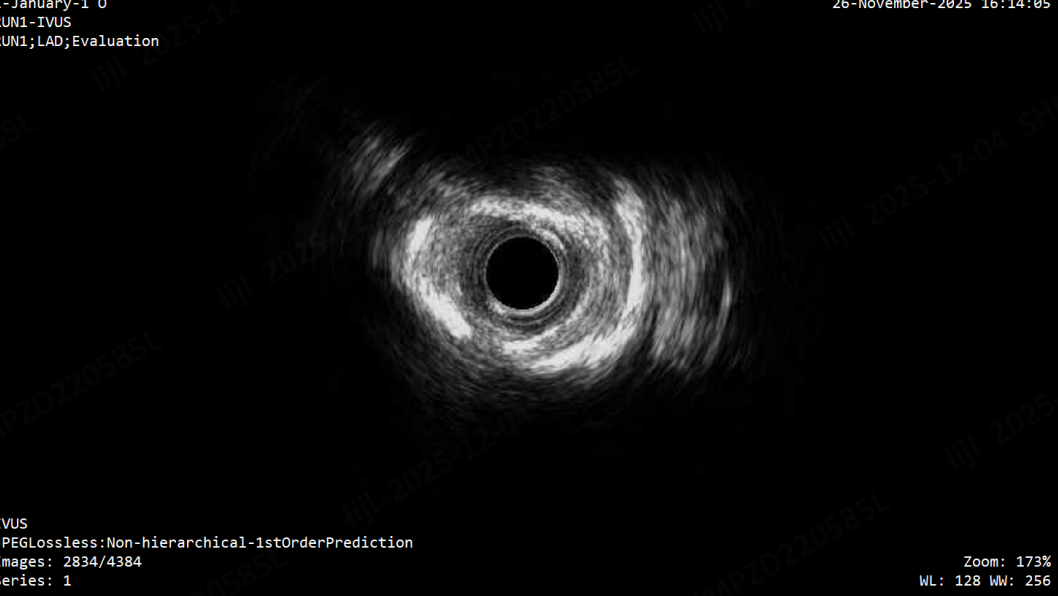

72岁,男性。患者于2025年11月26日行冠脉造影检查示:前降支近段可见约60%节段性狭窄,中段支架完全闭塞,D1开口可见约85%局限性狭窄,可见自身少许侧枝至前降支远段,回旋支近中段可见约50%节段性狭窄,原支架通畅,可见少许内膜增生。行IVUS检查提示前降支重度狭窄,重度钙化。与患者及家属沟通后同意介入治疗前降支,导入切割球囊、后扩球囊扩张病变,支架近段见狗骨头现象,反复修饰支架狗骨头现象不能消除,故原支架置入2.75*30mm药物球囊扩张病变,重复造影提示近段局部可见少许A型夹层,前向血流3级。本次为进一步处理前降支病变入院。

第一次术前IVUS示前降支重度狭窄,重度钙化